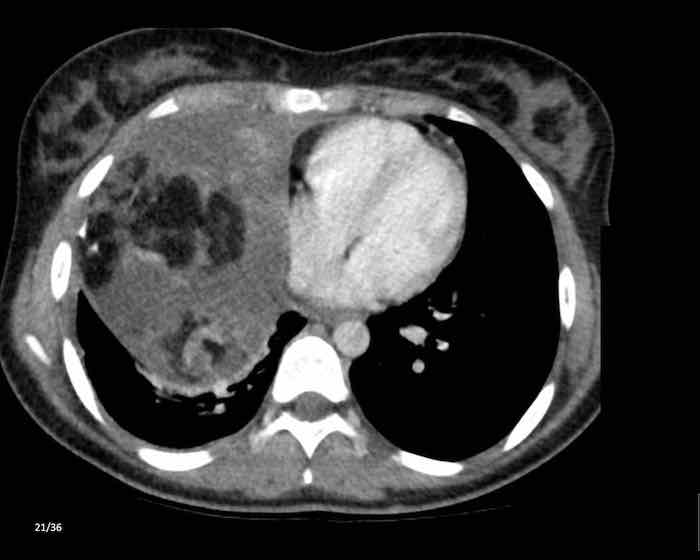

Các hình ảnh này của một nam giới 71 tuổi.

Trên CT ngực, tình cờ phát hiện một khối ở tuyến ức.

Hãy phân tích các hình ảnh. Nhận định của bạn là gì?

Hình ảnh

Một phần tổn thương có ngấm thuốc cản quang và có một số vôi hóa, có thể nằm ở thành nang.

Khi một tổn thương tuyến ức có thành phần đặc, nguyên tắc là… “khi còn nghi ngờ, hãy phẫu thuật cắt bỏ”.

Tổn thương đã được phẫu thuật cắt bỏ dựa trên kết quả CT và kết quả giải phẫu bệnh cho thấy đây là u tuyến ức dạng nang.